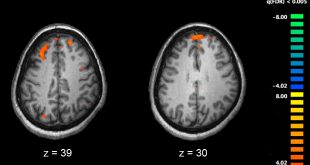

ادامهی نوشته“خوانش پریشی” از کجا شروع می شود؟/اختلال مغز در تطابق به نور و صدا

نوروسافاری | خوانش پریشی (dyslexia) برگرفته از کلمه ای لاتین به معنای تحت اللفظی «بد کلمگی!» است و اختلالی می باشد که بر توانایی خوب خواندن، درک مطالب مکتوب و حتی بر تلفظ و نوشتن مناسب فرد تاثیر می گذارد. این اختلال شایع ترین ناتوانی یادگیری مبتنی بر زبان است …